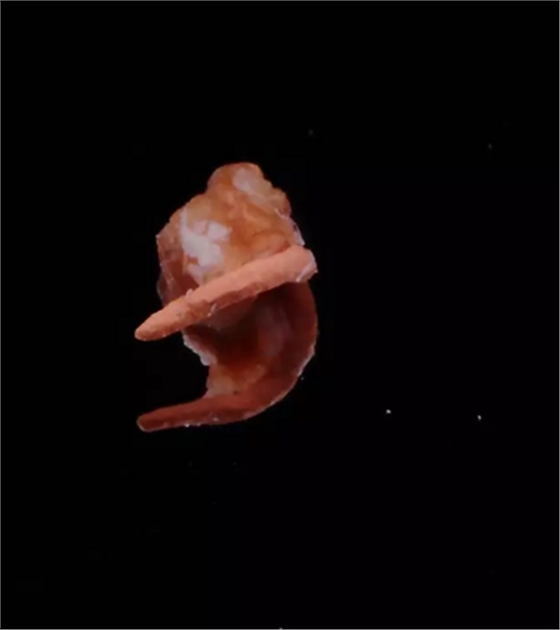

翻瓣去除側(cè)穿超出的牙膠尖

側(cè)穿超出的牙膠尖